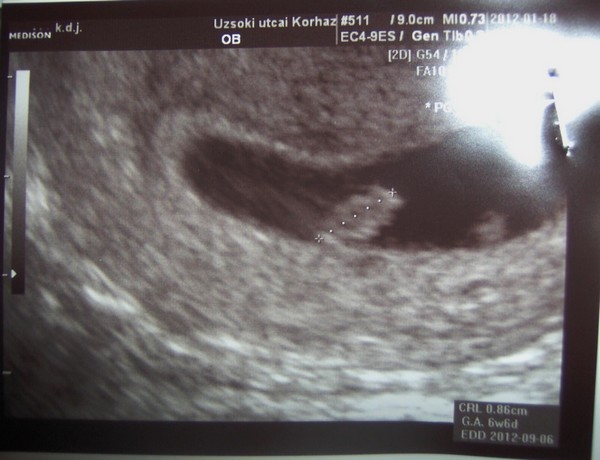

Az én lányom és kistesó BMC-s eredmény